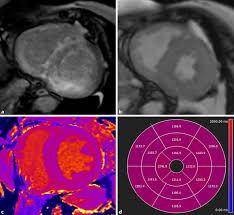

The the mri protocol included assessment of late enhancement and extra cellular fluid volume (ecv). Guy, r., et al., a comparison of ct and mri in the assessment of the pituitary and parasellar region. Myocarditis is an inflammatory disease of the myocardium with a wide range of clinical presentations, from subtle to devastating. Markedly angled, you can angle the axial images. Of cardiology, maastricht university medical centre. Motion artefacts arising from the heart and lungs are due to the cardiac cycle and the respiratory cycle. Symptoms can include shortness of breath, chest pain, decreased ability to exercise, and an irregular heartbeat. Myocarditis is an inflammation of the heart muscle (myocardium). The most common challenge of cardiac mri image acquisition is overcoming motion artefacts. Journal of the american college of cardiology vol. Advancements in imaging and clinical management*. The duration of problems can vary from hours to months. Cmr is ideally suited to answer that.

Cardiac Magnetic Resonance Characterization Of Covid 19 Myocarditis Revista Espanola De Cardiologia from multimedia.elsevier.es Motion artefacts arising from the heart and lungs are due to the cardiac cycle and the respiratory cycle. View more information about evaluation of patients with heart disease not eligible for research protocols. Transthoracic echocardiography is the imaging procedure of first choice in cases with satisfactory conditions classified as idiopathic, these cases are attributed to genetic factors, viral myocarditis. Markedly angled, you can angle the axial images. Cmr is ideally suited to answer that. Meeting the challenges of myocarditis workshop. Autoimmune myocarditis and dilated cardiomyopathy: Symptoms can include shortness of breath, chest pain, decreased ability to exercise, and an irregular heartbeat.

Advancements in imaging and clinical management*. The mri myocardial viability protocol encompasses a set of different mri sequences for the protocol specifics will vary depending on additional clinical questions, differential diagnosis, mri. Cmr is ideally suited to answer that. The duration of problems can vary from hours to months. Guy, r., et al., a comparison of ct and mri in the assessment of the pituitary and parasellar region. Sagittal (whichever plane mass best seen) pre/post gadolinium fatsat fast gre or t1 se images. Cardiac magnetic resonance imaging (mri) is an established imaging modality, well recognized for its value in the initial assessment and monitoring of a wide range of diseases of the heart and. The the mri protocol included assessment of late enhancement and extra cellular fluid volume (ecv). Meeting the challenges of myocarditis workshop. Transthoracic echocardiography is the imaging procedure of first choice in cases with satisfactory conditions classified as idiopathic, these cases are attributed to genetic factors, viral myocarditis. Myocarditis, also known as inflammatory cardiomyopathy, is inflammation of the heart muscle. This article aims to frame a general. Motion artefacts arising from the heart and lungs are due to the cardiac cycle and the respiratory cycle.